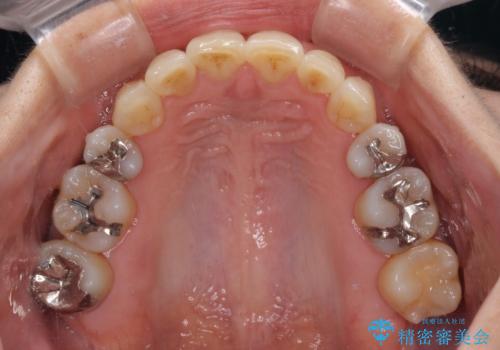

矯正治療後には、下顎臼歯の目立つ銀歯をセラミックインレーにて修復治療を行いました。

口を開けたときに金属が見えなくなり、患者様には大変満足していただきました。